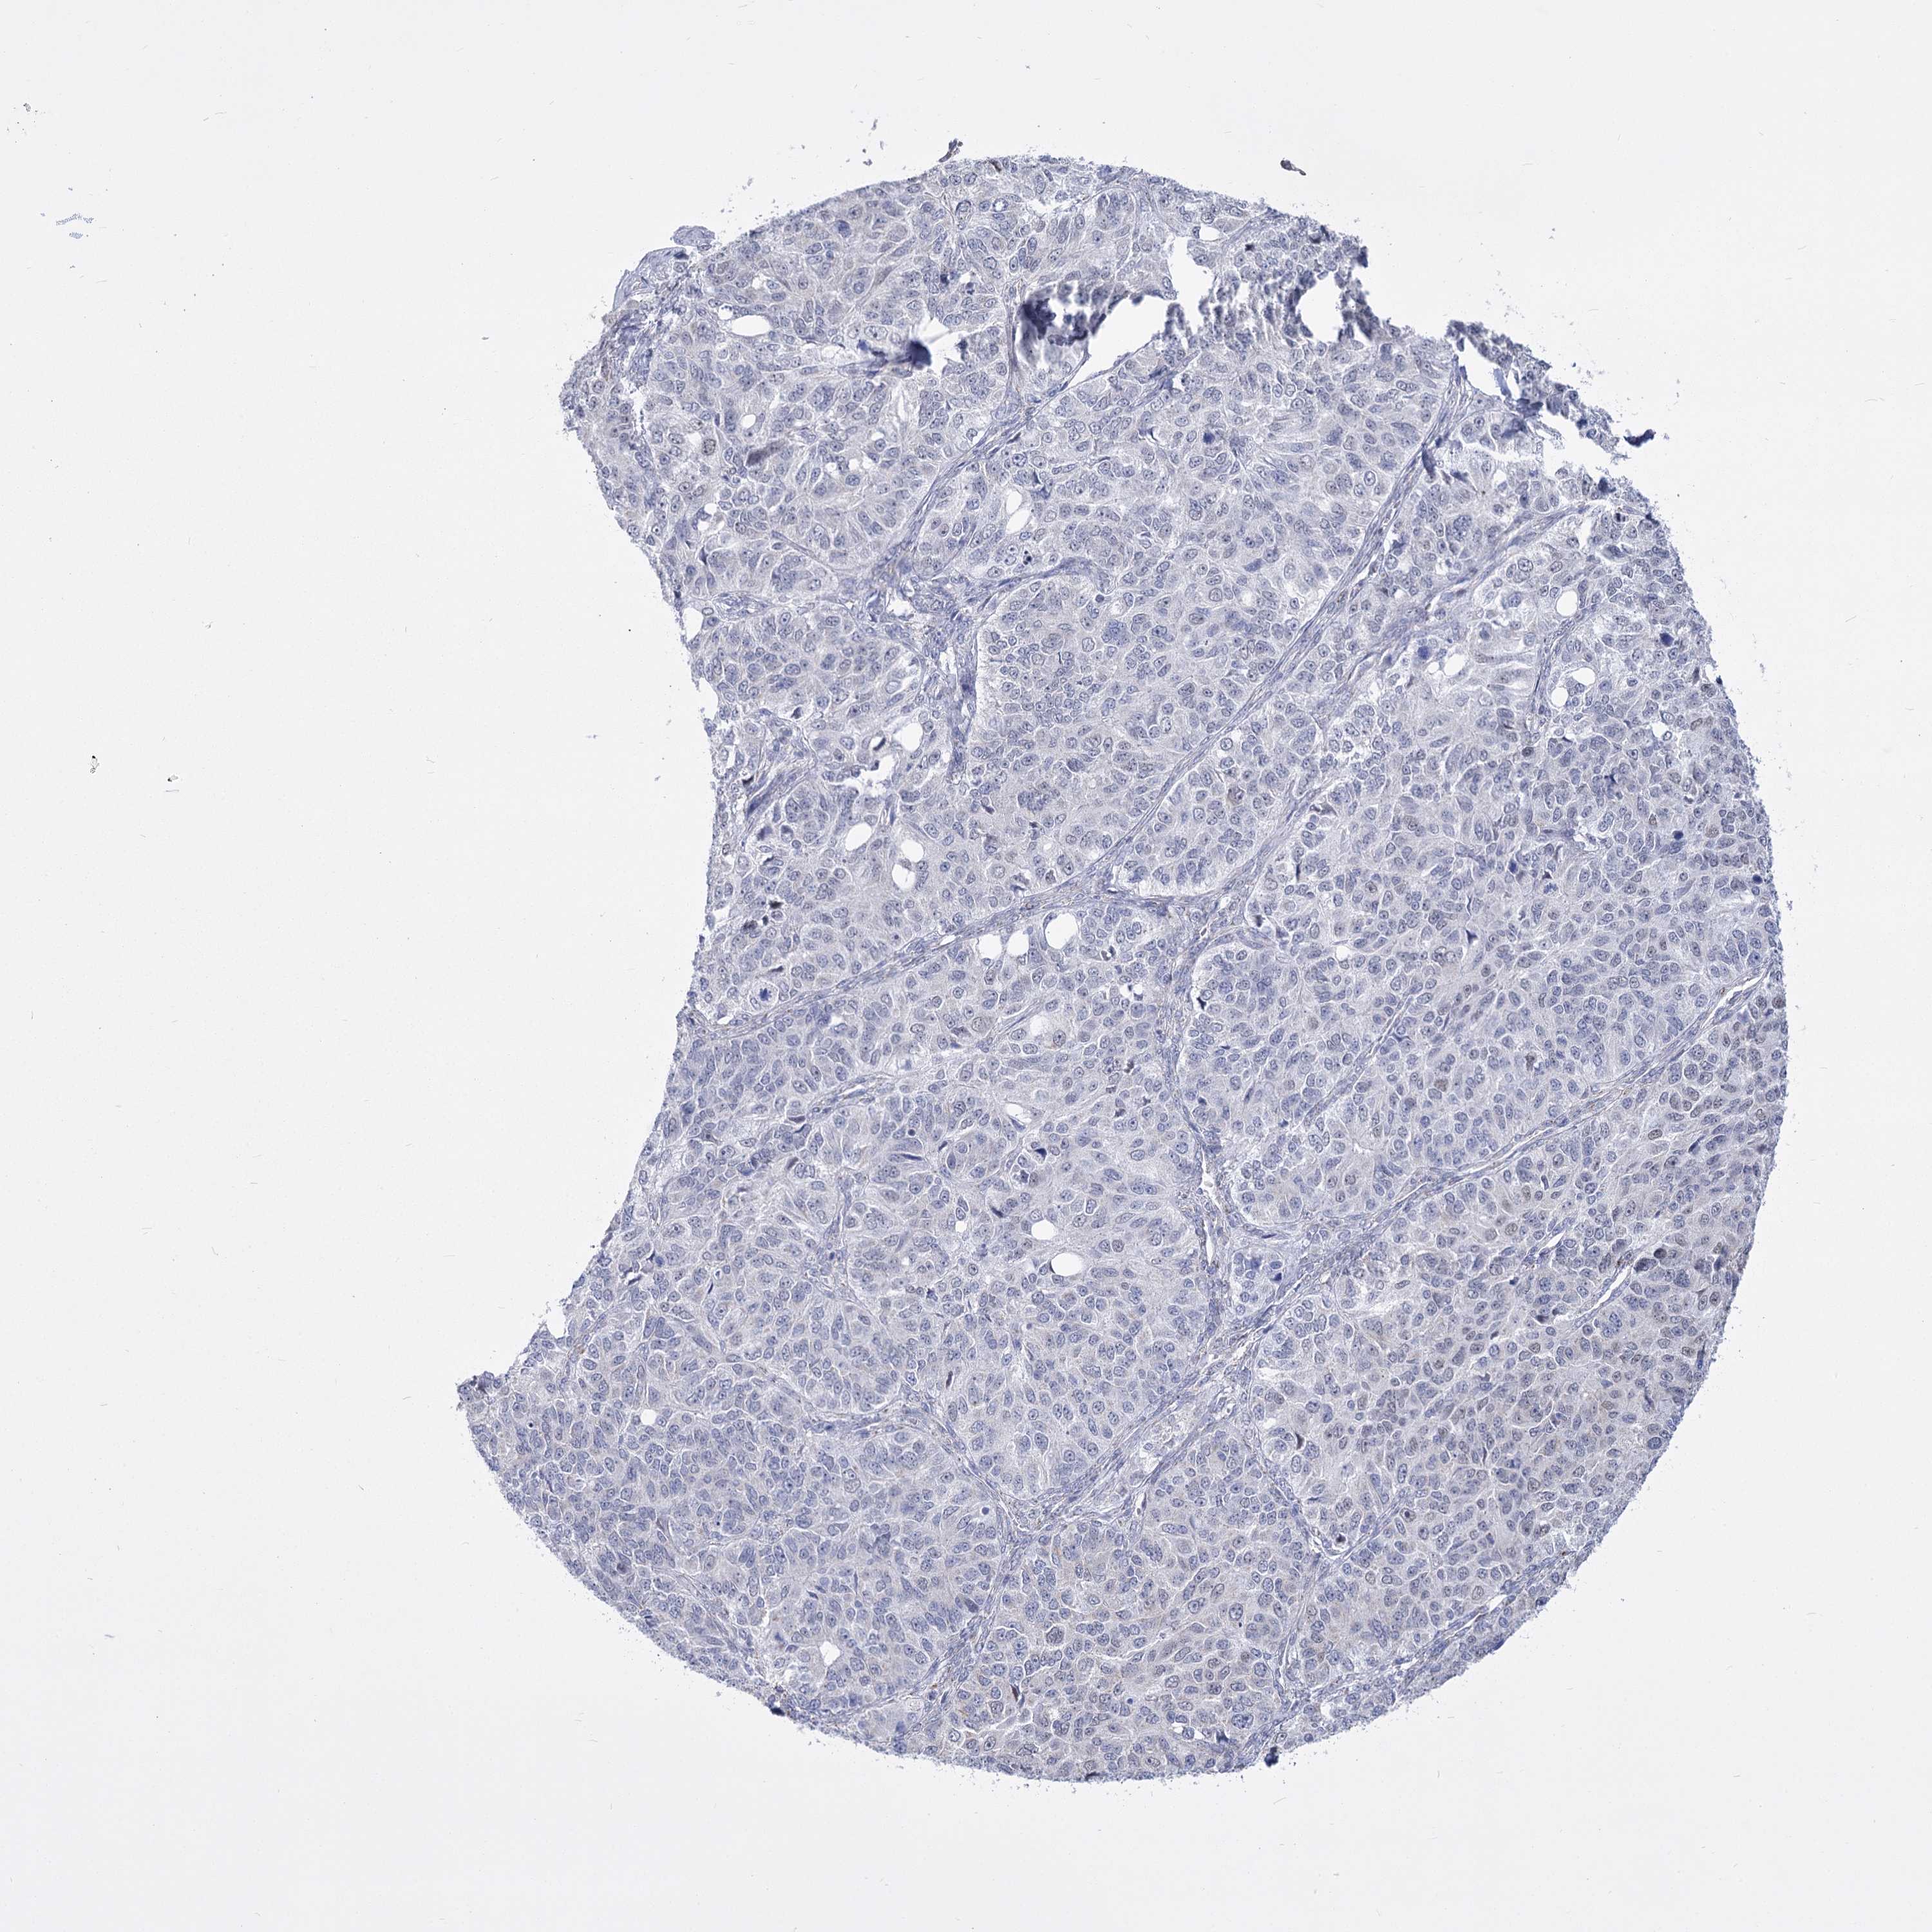

OVARIAN CANCER - Protein expressioni

A mouse-over function shows sample information and annotation data. Click on an image to view it in a full screen mode. Samples can be filtered based on level of antibody staining by selecting one or several of the following categories: high, medium, low and not detected. The assay and annotation is described here.

Note that samples used for immunohistochemistry by the Human Protein Atlas do not correspond to samples in the TCGA dataset.

Antibody stainingi

Antibody staining in the annotated cell types in the current human tissue is reported as not detected, low, medium, or high, based on conventional immunohistochemistry profiling in selected tissues. This score is based on the combination of the staining intensity and fraction of stained cells.

Each image is clickable and will lead to virtual microscopy that enables deeper exploration of all samples and also displays staining intensity scores, fraction scores and subcellular localization as well as patient and tissue information for each sample.

Antibody HPA036744

Antibody HPA036745

Antibody CAB033794

Cystadenocarcinoma, serous, NOS

Carcinoma, endometroid

Cystadenocarcinoma, mucinous, NOS

Carcinoma, NOS